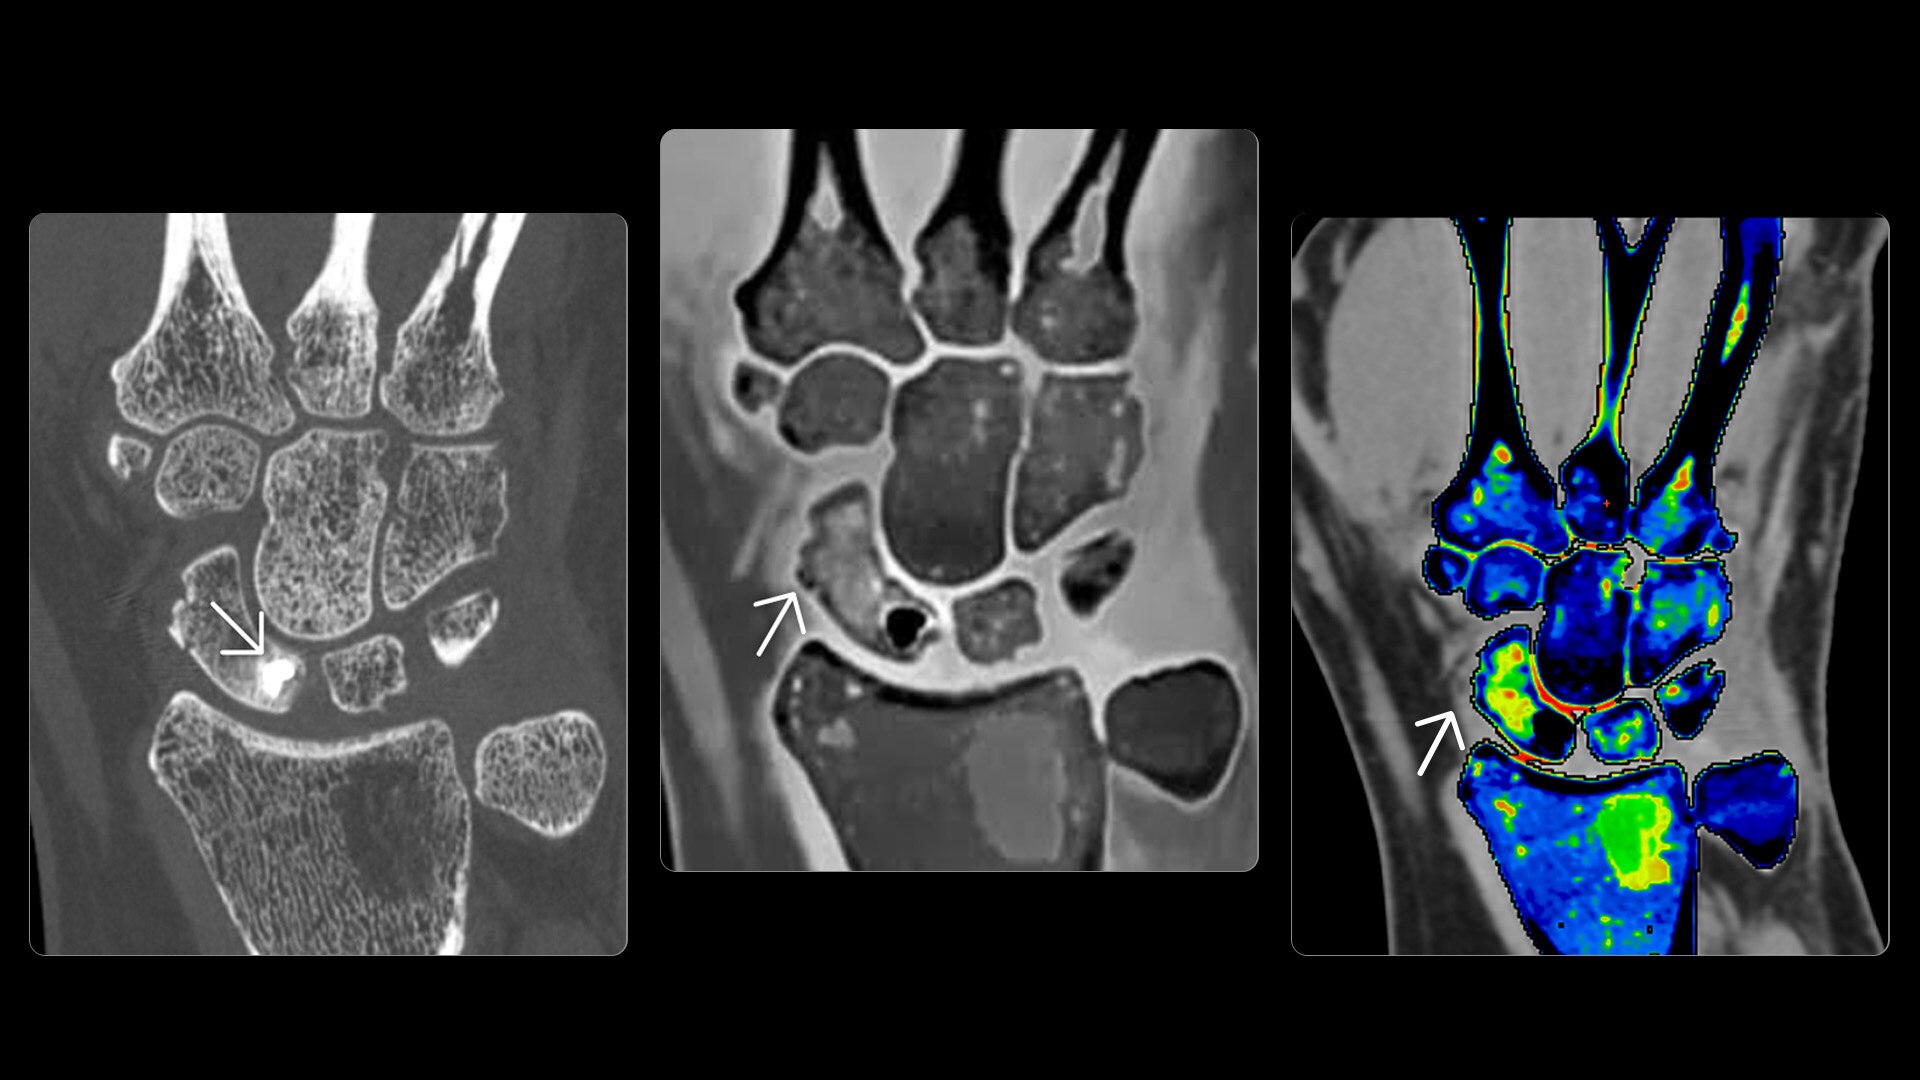

On-demand spectral imaging enabled by 8-energy bins

Our advanced spectral imaging capabilities are intended to allow you to experience the difference between seeing and knowing so you can confidently detect, characterize and monitor disease.

Photonova Spectra is also designed to enhance material separation for tissue characterization and disease quantification, bringing potentially greater diagnostic confidence in every acquisition across care areas.

A full range of spectral imaging series is generated natively on console and available for transfer to PACS. The full-fidelity spectral data acquisition is intended to provide native DICOM images and material maps to support clinical diagnosis, with improvements of up to 4x enhanced energy discretization1, 2x higher material map spatial resolution2, and 2x improved iodine detectability3.

1. Than compared to dual energy CT.

2. Compared to Revolution Apex with Gemstone Spectral Imaging (GSI), based on 10% MTF measurements in iodine (water) phantom images using the highest available resolution kernel on Photonova Spectra and on Revolution Apex with GSI at matched dose. 10 mg/mL iodine concentration was used for the measurement.

3. Iodine detectability defined as the lowest iodine concentration the system can detect. Photonova Spectra delivers a 2x and greater improvement in iodine detectability, compared to Revolution Apex. It has the ability to detect iodine concentrations down to 0.2 mg/mL at a radiation dose of 8 mGy, using Gammex Multi‑Energy CT Phantom with water and a 0.2 mg/mL iodine insert. Dose based on a 32 cm dosimetry phantom.